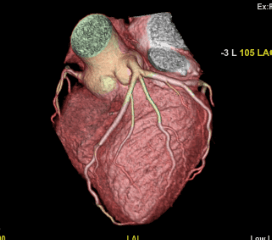

Coronary Angiogram

A CT Coronary Angiogram is a non-invasive imaging test that uses a CT scanner, and contrast dye to create detailed 3D pictures of your heart's arteries, revealing plaque, blockages, or narrowing (stenosis) that can cause heart problems like chest pain.

3D Vessel Analysis